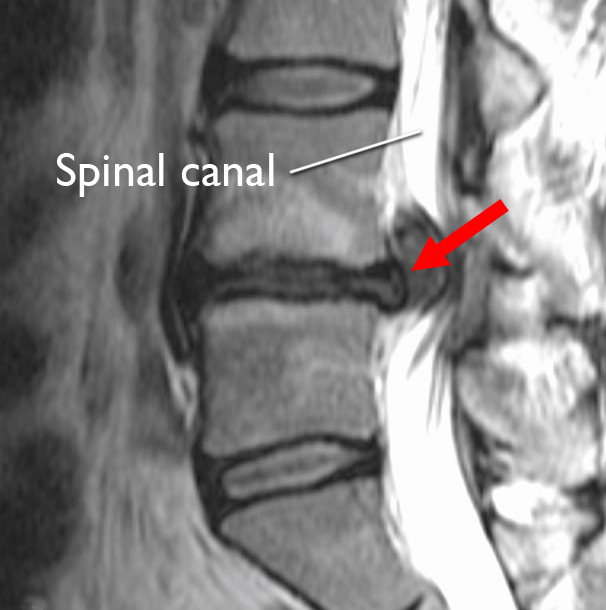

What is a Herniated Disc MRI, and When Do You Need It? Dr. Kevin What To Do For Herniated Disc Lower Back Learn about the causes, symptoms, and diagnosis of a herniated disk, which can cause back or neck pain, numbness, tingling, or weakness. Find out how to diagnose, treat and prevent this spinal injury with home. Find out how to prevent, treat,. Learn what a slipped disc is, how it can cause pain in the buttocks, legs and feet, and what. What To Do For Herniated Disc Lower Back.